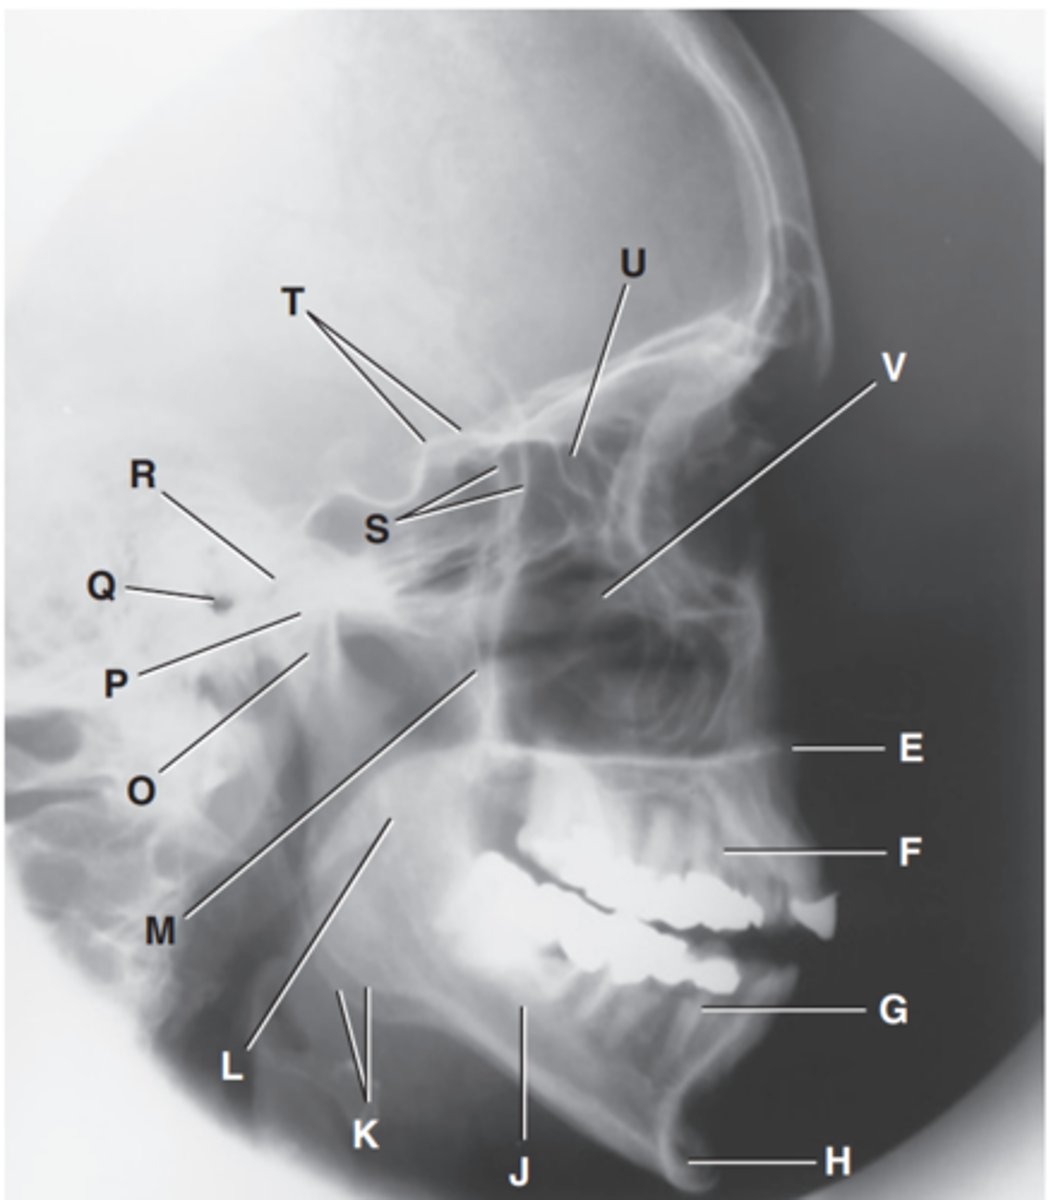

Zygomatic arch

Label A

Right zygomatic bone

Label B

Right nasal bone

Label C

Frontal process of right maxilla

Label D

Anterior nasal spine

Label E

Alveolar process of maxilla

Label F

Alveolar process of mandible

Label G

Mentum or mental protuberance

Label H

Mental foramen

Label I

Body of mandible

Label J

Angle (gonion)

Label K

Ramus of mandible

Label L

Coronoid process

Label M

Mandibular notch

Label N

Neck of mandibular condyle

Label o

Condyle or head of mandible

Label P

EAM

Label Q

TM fossa of temporal bone

Label R

Greater wings of sphenoid

Label S

Lesser wings of sphenoid with anterior clinoid processes

Label T

Ethmoid sinuses between orbits

Label U

Body of maxilla containing maxillary sunuses

Label V